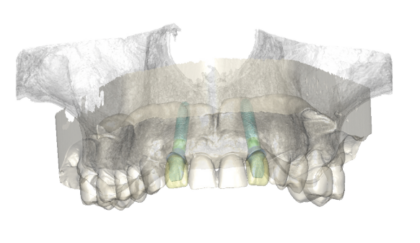

歯科用CTを用いた正確な診断

歯科用CTは、顎の骨の状態を3D画像で詳細に把握できる先進的な機器です。これにより、骨の厚さや密度を正確に確認でき、インプラント治療の計画をより精密に立てることができるため、治療の成功率を大幅に向上させます。

複雑な歯の根の状態も精密に診断できるため安全なインプラント治療に必須です。

シミュレーションソフトで事前確認

取得したCT画像をもとにシミュレーションソフトで治療計画を作成し、インプラントの埋入位置や角度を事前に確認します。このシミュレーションにより、手術の正確性が増し、歯茎を切開する範囲を最小限に抑えることが可能です。その結果、術後の治りが早まり、身体への負担も軽減されます。